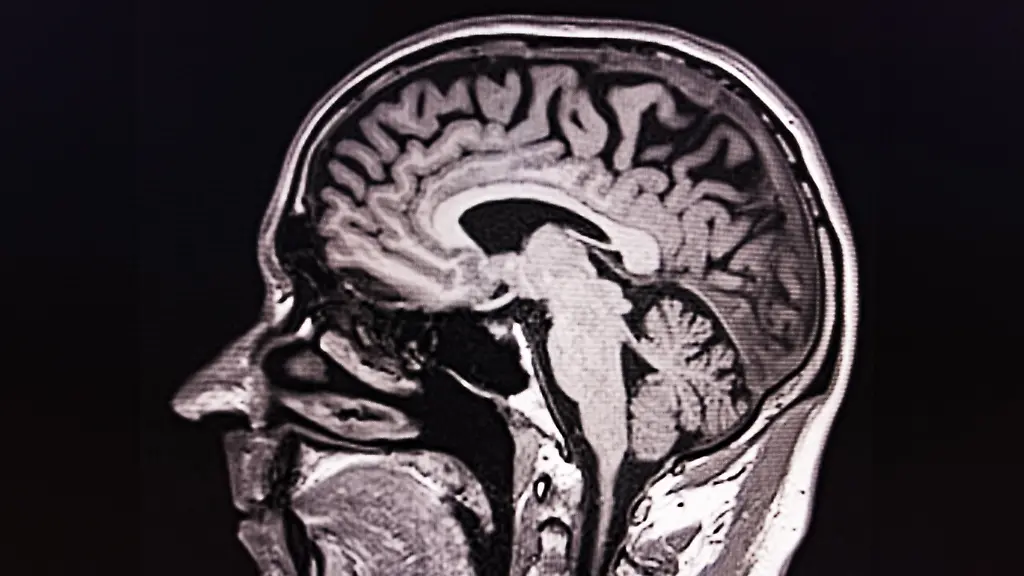

Mit einer Magnetresonanztomografie lässt sich die Struktur des Gehirns messbar darstellen.

(Foto: picture alliance / imageBROKER)